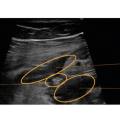

L’échographie permet la visualisation de l’ensemble du cadre colique, de la dernière anse iléale et des anses grêles, par balayage de l’épigastre jusqu’au pelvis. Les points analysés sont l’épaisseur pariétale (fig. 1), le signal doppler, les anomalies de la graisse mésentérique, la stratification pariétale, le péristaltisme, la présence d’ulcérations, d’adénopathies ou de complications (fistule, abcès, sténose ou épanchement intra-abdominal [fig. 2]). L’examen échographique permet de localiser ces éléments sémiologiques et de préciser la longueur de l’atteinte, le cas échéant.3